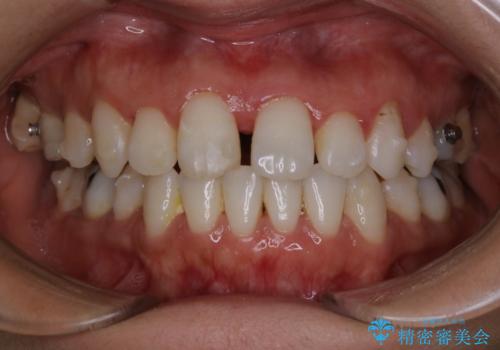

インビザラインでの矯正治療でアタッチメントset前のPMTC